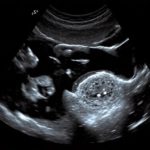

Когда речь заходит о диагностике персистенции фолликула, важно отметить, что она не всегда очевидна. Многие женщины могут даже не подозревать, что у них есть такая проблема. Обычно персистенция фолликула выявляется в ходе ультразвукового исследования яичников, которое может быть назначено в рамках профилактического осмотра или при наличии каких-либо жалоб. На УЗИ врач может увидеть фолликул, который не рассосался, а остался в яичнике.